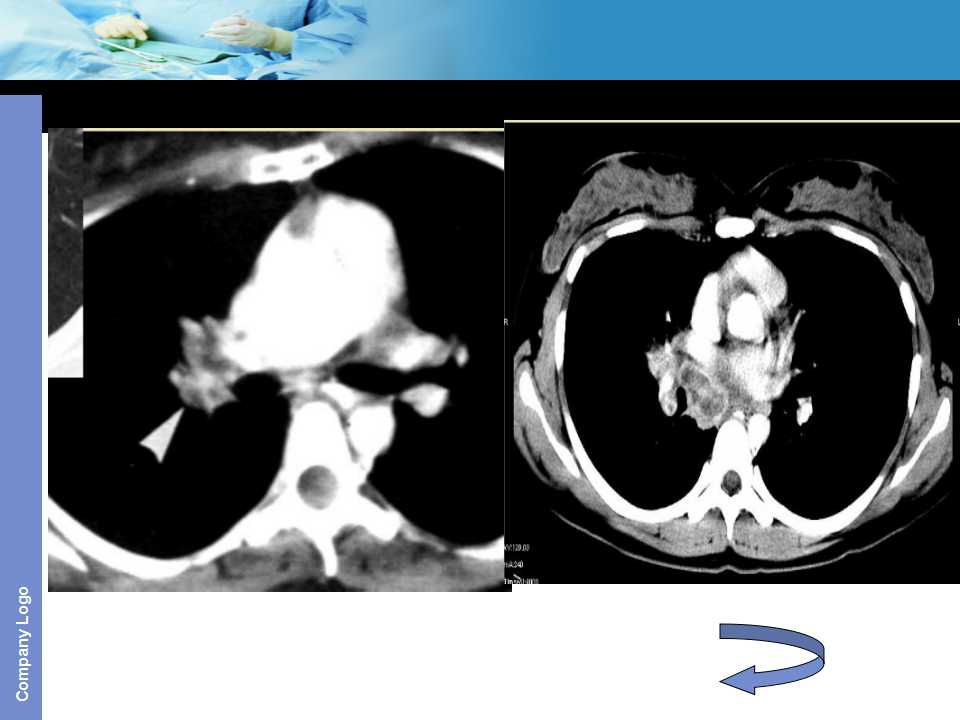

肺癌影像诊断